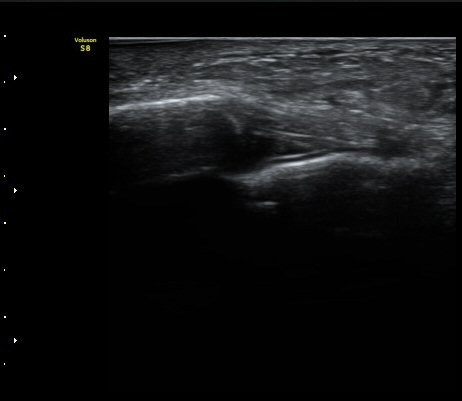

Àδë Á¾°ñºÎÂøºÎ Á¾´Ü¸é°Ë»ç¿Í Ⱦ´Ü¸é°Ë»ç¿¡¼­ Á¾°ñÀÇ °ß¿­°ñÀýÀÌ °üÂ÷µÊ(»çÁø 4, 5).